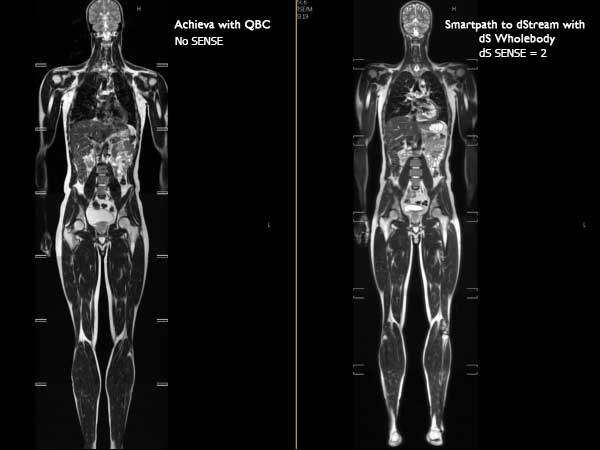

Total Body Imaging

Whole Body imaging